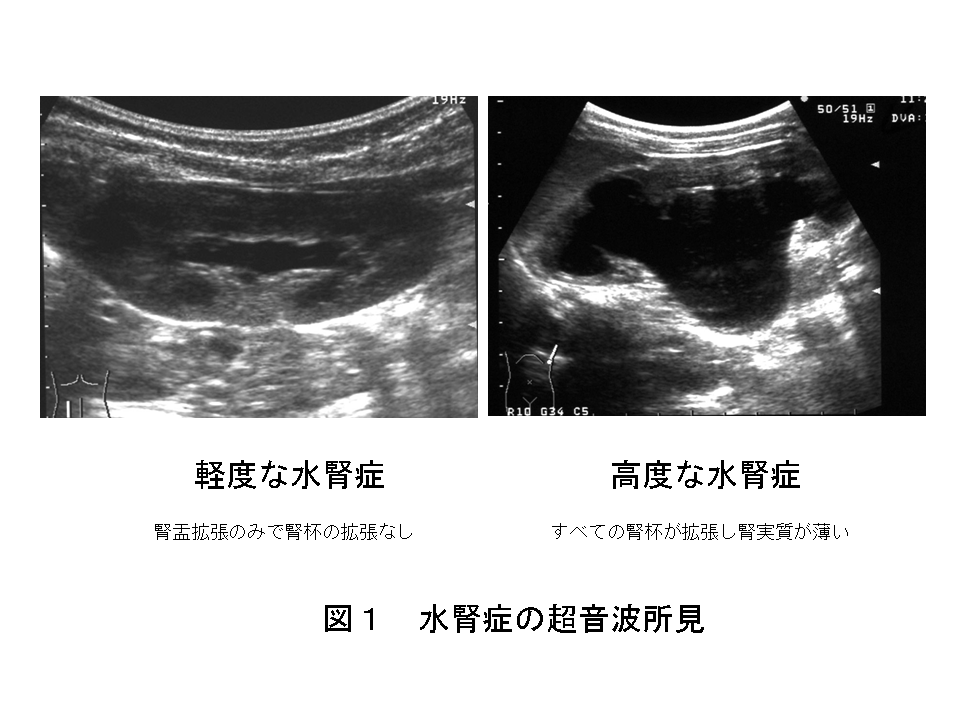

診断は超音波検査で比較的容易に診断でき、それによって水腎の程度もわかります(図1:ここをクリック)。

水腎症はすぐに治療が必要なわけではなく、軽度な水腎ではそのほとんどは自然治癒します。

しかし,高度な水腎症では腎機能の低下がないかどうかの検査が必要です。レノグラム・腎シンチグラムといったRI検査(核医学検査です)が有用です。腎機能の低下がみられず水腎症が進行しなければ、その多くは自然軽快してくるので、手術は行わず経過を観察するのが原則です。